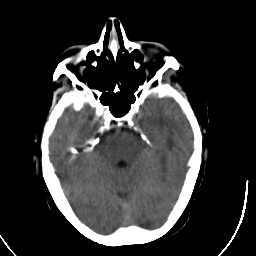

Stroke CT #3 -- Slice #7

[Home][Help][Clinical] Slice 7